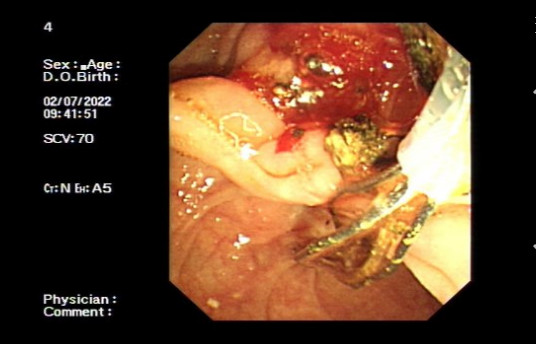

ERCP手术中

术中,郑东林主任与助手们运用娴熟的技术及丰富的操作经验,顺利完成ERCP、EST、胆道结石取石、切开引流等操作,大量乳白色脓液当即排出,并取出两颗1CM大小结石,留置鼻胆管,再次照影未见明显充盈缺损。整个手术过程仅20分钟,十分顺利。